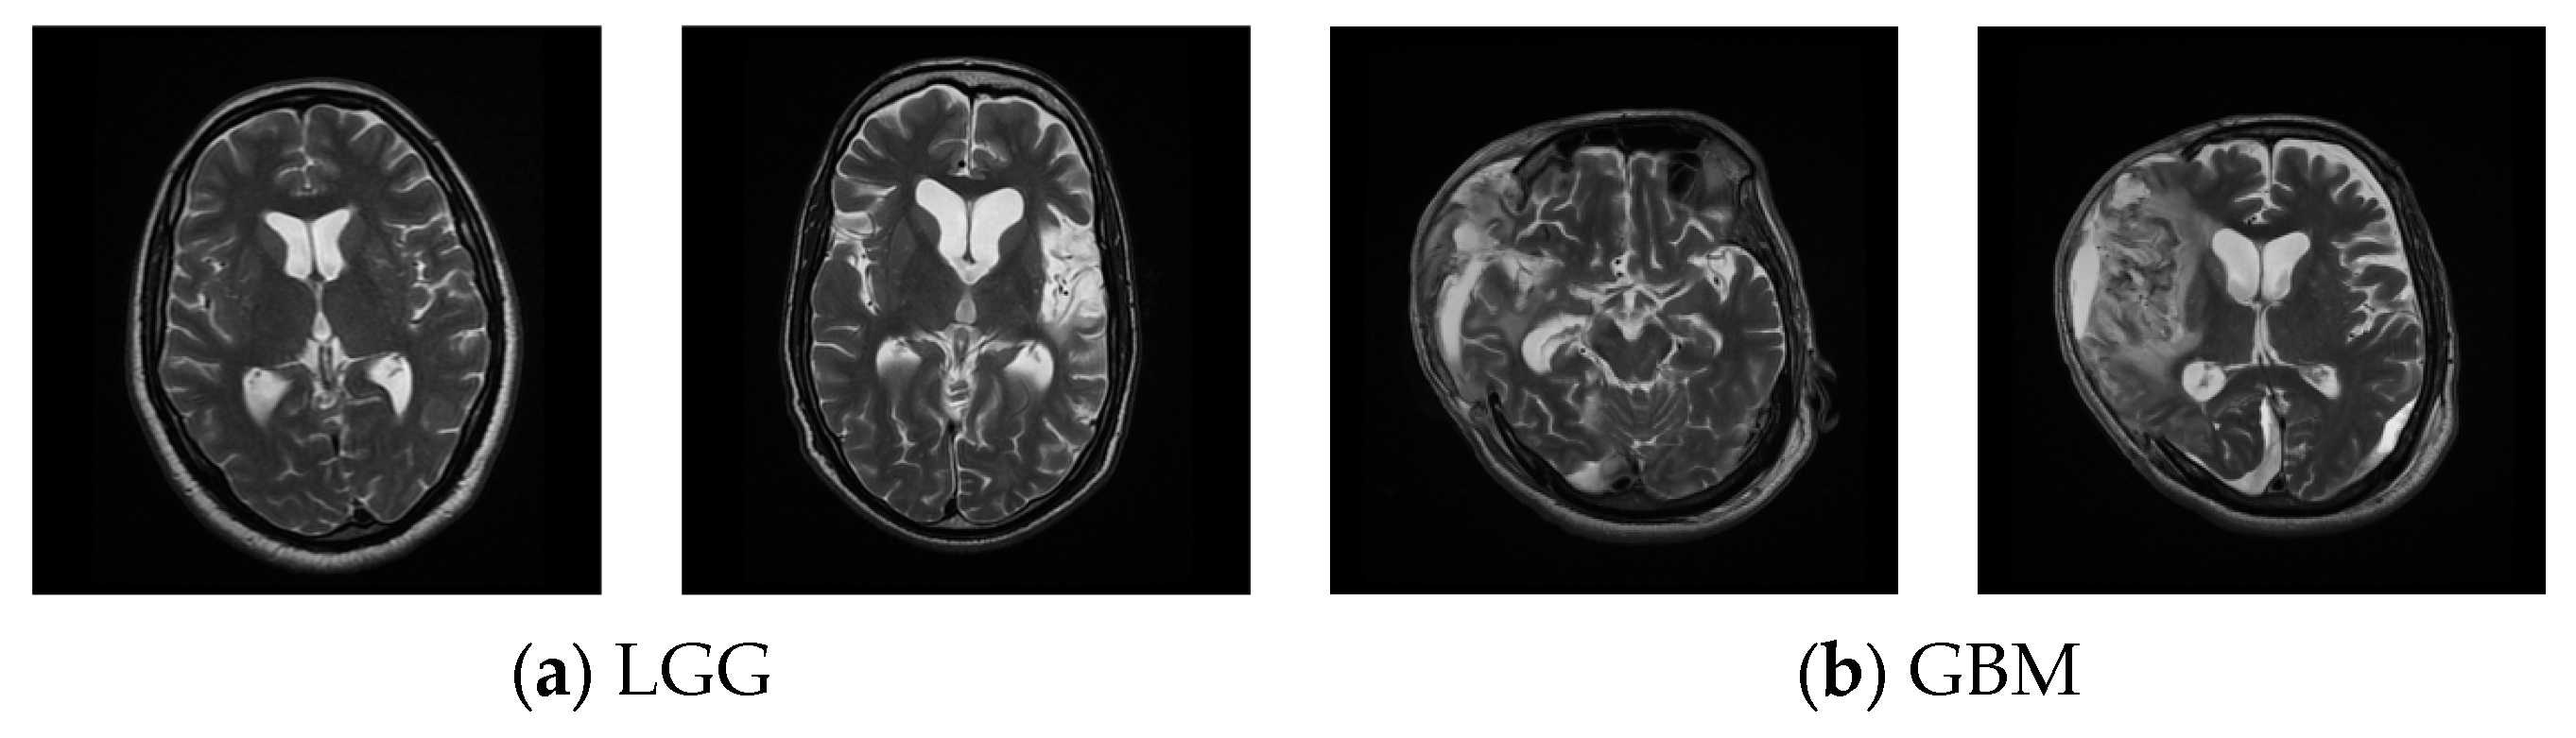

3.2. MRI Dataset